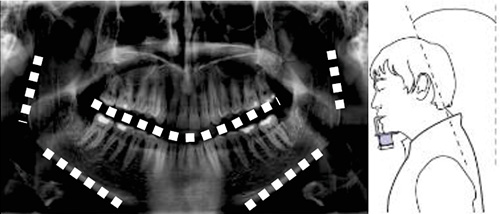

咬合平面が「V字」にカーブ

→顎の引きすぎ、チンレストが低い